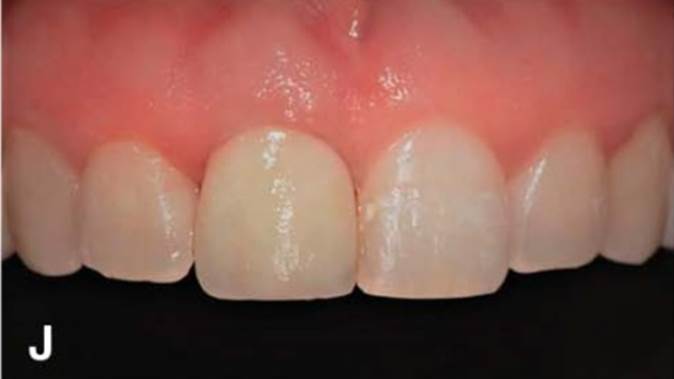

Clinical case: Replacement of fractured central incisor (#11) with immediate implant

& Root Membrane Technique

- Courtesy of Dr. Miltiadis Mitsias, Greece -

AnyRidge, Root Membrane Technique, retrospective study, long-term study, immediate implants, bone resorption, bone preservation, Dr. Miltiadis Mitsias,survival, success, maxillary anterior, single replacement

AnyRidge implant system, Root Membrane kit

The Root Membrane Technique: A retrospective clinical study with up to 10 years of follow-up./Implant Dent. 2018 Oct;27(5):564-574

https://www.ncbi.nlm.nih.gov/pubmed/30161062